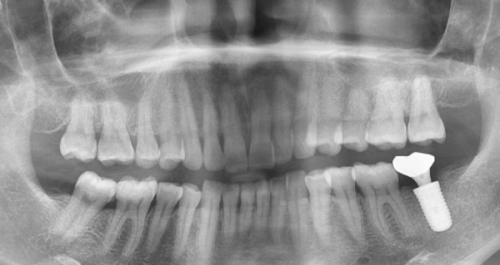

(二)牙槽骨条件

上门牙种植需要足够的骨量来支撑植体。要是牙槽骨萎缩或吸收了,可能得进行骨增量手术(植骨),增加骨密度后才能种植。不过现在植骨技术特别成熟,大家不用太担心。